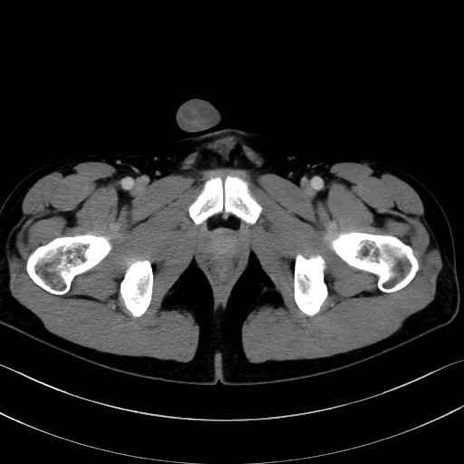

短内転筋(Adductor brevis) のCT画像の解剖

短内転筋 (Adductor brevis)